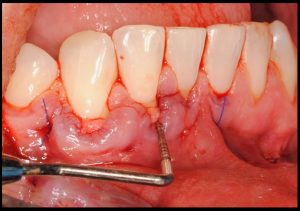

Exploración inicial:

Objetivos periodontales: Mediante ingerto de tejido conectivo subepitelial de paladar con técnica de tunelización.

Fotografías del proceso: